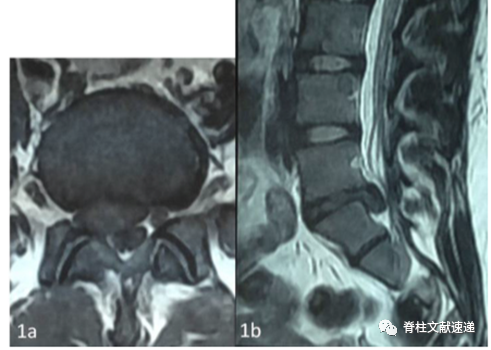

该文献报道了一例21岁女性患者,以腰背部疼痛伴右下肢放射痛,尿失禁3天为主诉。右侧直腿抬高试验阳性(<20度)。右侧拇长伸肌和胫骨前肌力量下降。患者既往淋巴瘤曾进行5次化疗,安排进行了MR检查,如下图。随即安排了手术。

到手术室后才发现患者右侧臀部和膝盖处水泡、破溃和红斑,如下图。咨询了皮肤科医师诊断为带状疱疹。我们结合MR认为可能是带状疱疹与椎间盘突出并存,仍准备进行手术治疗。再次通过PACS系统查看MR时发现存在存在同名同姓患者,MR并非我们该患者的结果,而该患者MR是完全正常的!!随停止手术,给予阿昔洛韦、加巴喷丁治疗,10天后症状明显缓解,3月后完全缓解。